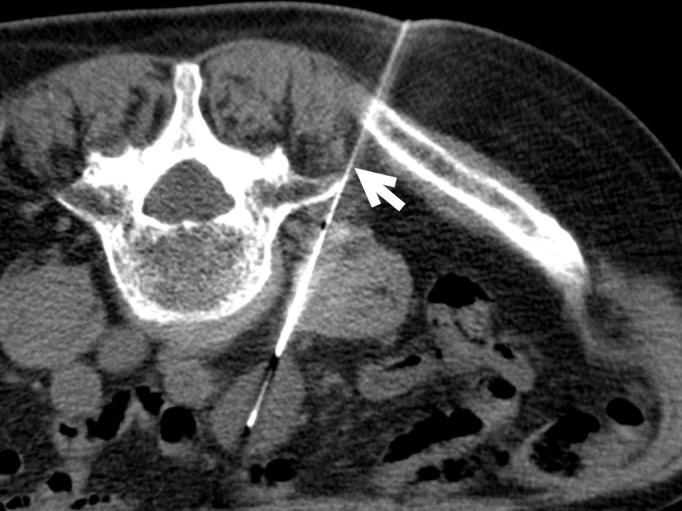

Materials: we present the case of an 82-year-old male patient with a recent diagnosis of moderately differentiated adenocarcinoma of the colon and a hypermetabolic periaortic nodule as an incidental finding.

Results: percutaneous biopsy of the periaortic nodule confirmed the diagnosis of schwannoma. At one year of follow-up, growth of the schwannoma has been demonstrated. There are no signs of progression of his oncological disease.